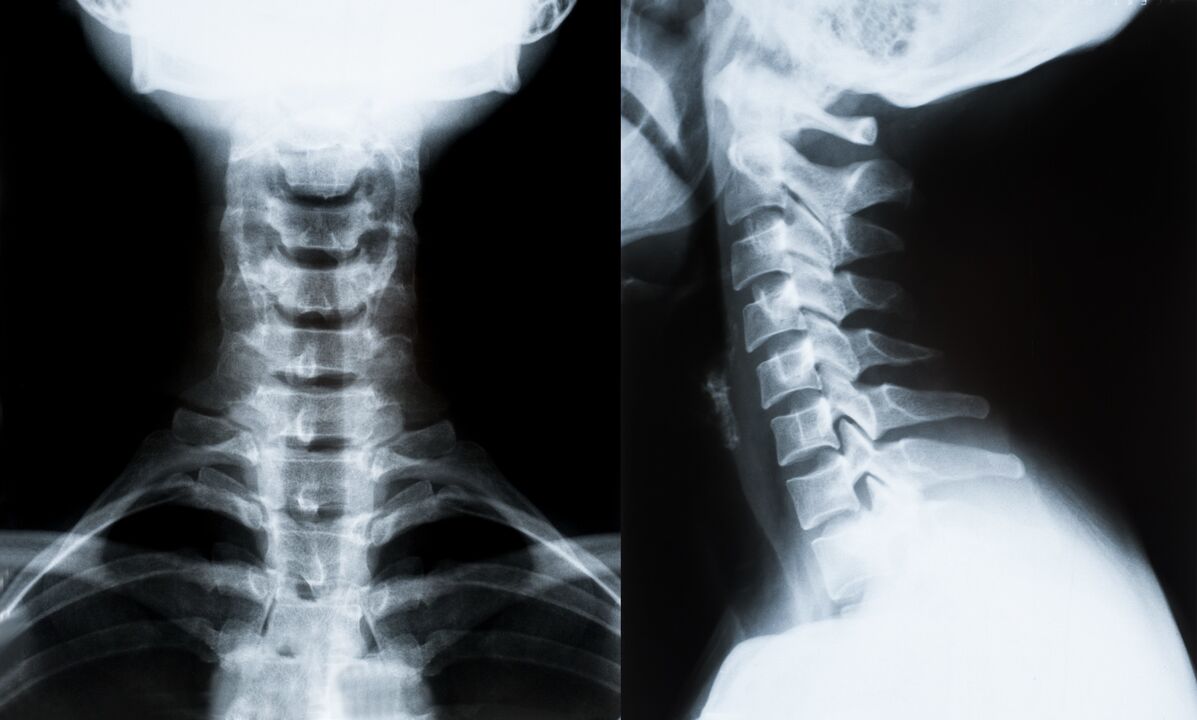

Trápaga bizkarrezurra osteokondrosiaren diagnostiko eta tratamendua zehazteko metodo nagusiak:

- X izpiak. Diagnostiko metodo gutxien eraginkorra, baina tradizionala.

- Erresonantzia magnetikoa diagnostiko metodorik eraginkorrena da. Gaixoaren azterketa mota honekin, beharrezko egitura guztiak ikusten dira.

- Aldaketak neurtu behar badira, ordenagailu bidezko tomografia erabiltzen da. Herniak eta beste gauza batzuen presentzia zehazten du.

- Azken metodoa ultrasoinu duplex eskaneatzea da. Ikerketa-metodo honek arterien odol-fluxuaren abiadura zehazten du.

Ezinezkoa da etxean bizkarrezurreko gaixotasuna zehaztasunez zehaztea.